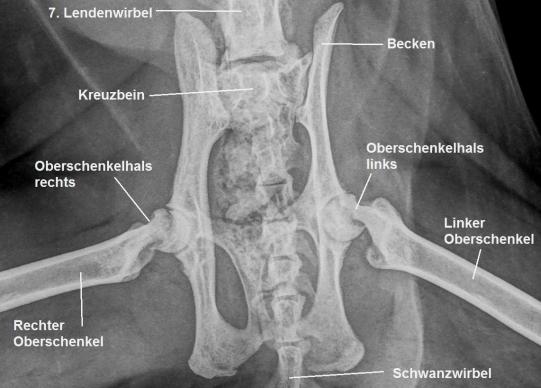

Charly wird orthopädisch untersucht. Er zeigt ein stark verändertes Gangbild in der Hinterhand: Die Katze läuft mit gekrümmtem Rücken, untergeschobenen Hinterbeinen und wie auf Eiern. Die Oberschenkelmuskulatur ist beidseits schlecht ausgebildet, und das Strecken der Hüftgelenke ist ganz offensichtlich schmerzhaft. In einer kurzen Sedation werden deshalb Röntgenaufnahmen des Beckens und der Hüftgelenke angefertigt. Hier ist die Ursache des Problems ersichtlich: An beiden Oberschenkelhälsen ist eine Bruchlinie zu sehen; die Oberschenkelköpfe sind beidseits vom Oberschenkelhals-Knochen abgebrochen!

Die Röntgenveränderungen erklären die Gangprobleme von Charly vollständig - er leidet unter einer beidseitigen sogenannten metaphysealen Osteopathie der Oberschenkelhälse.